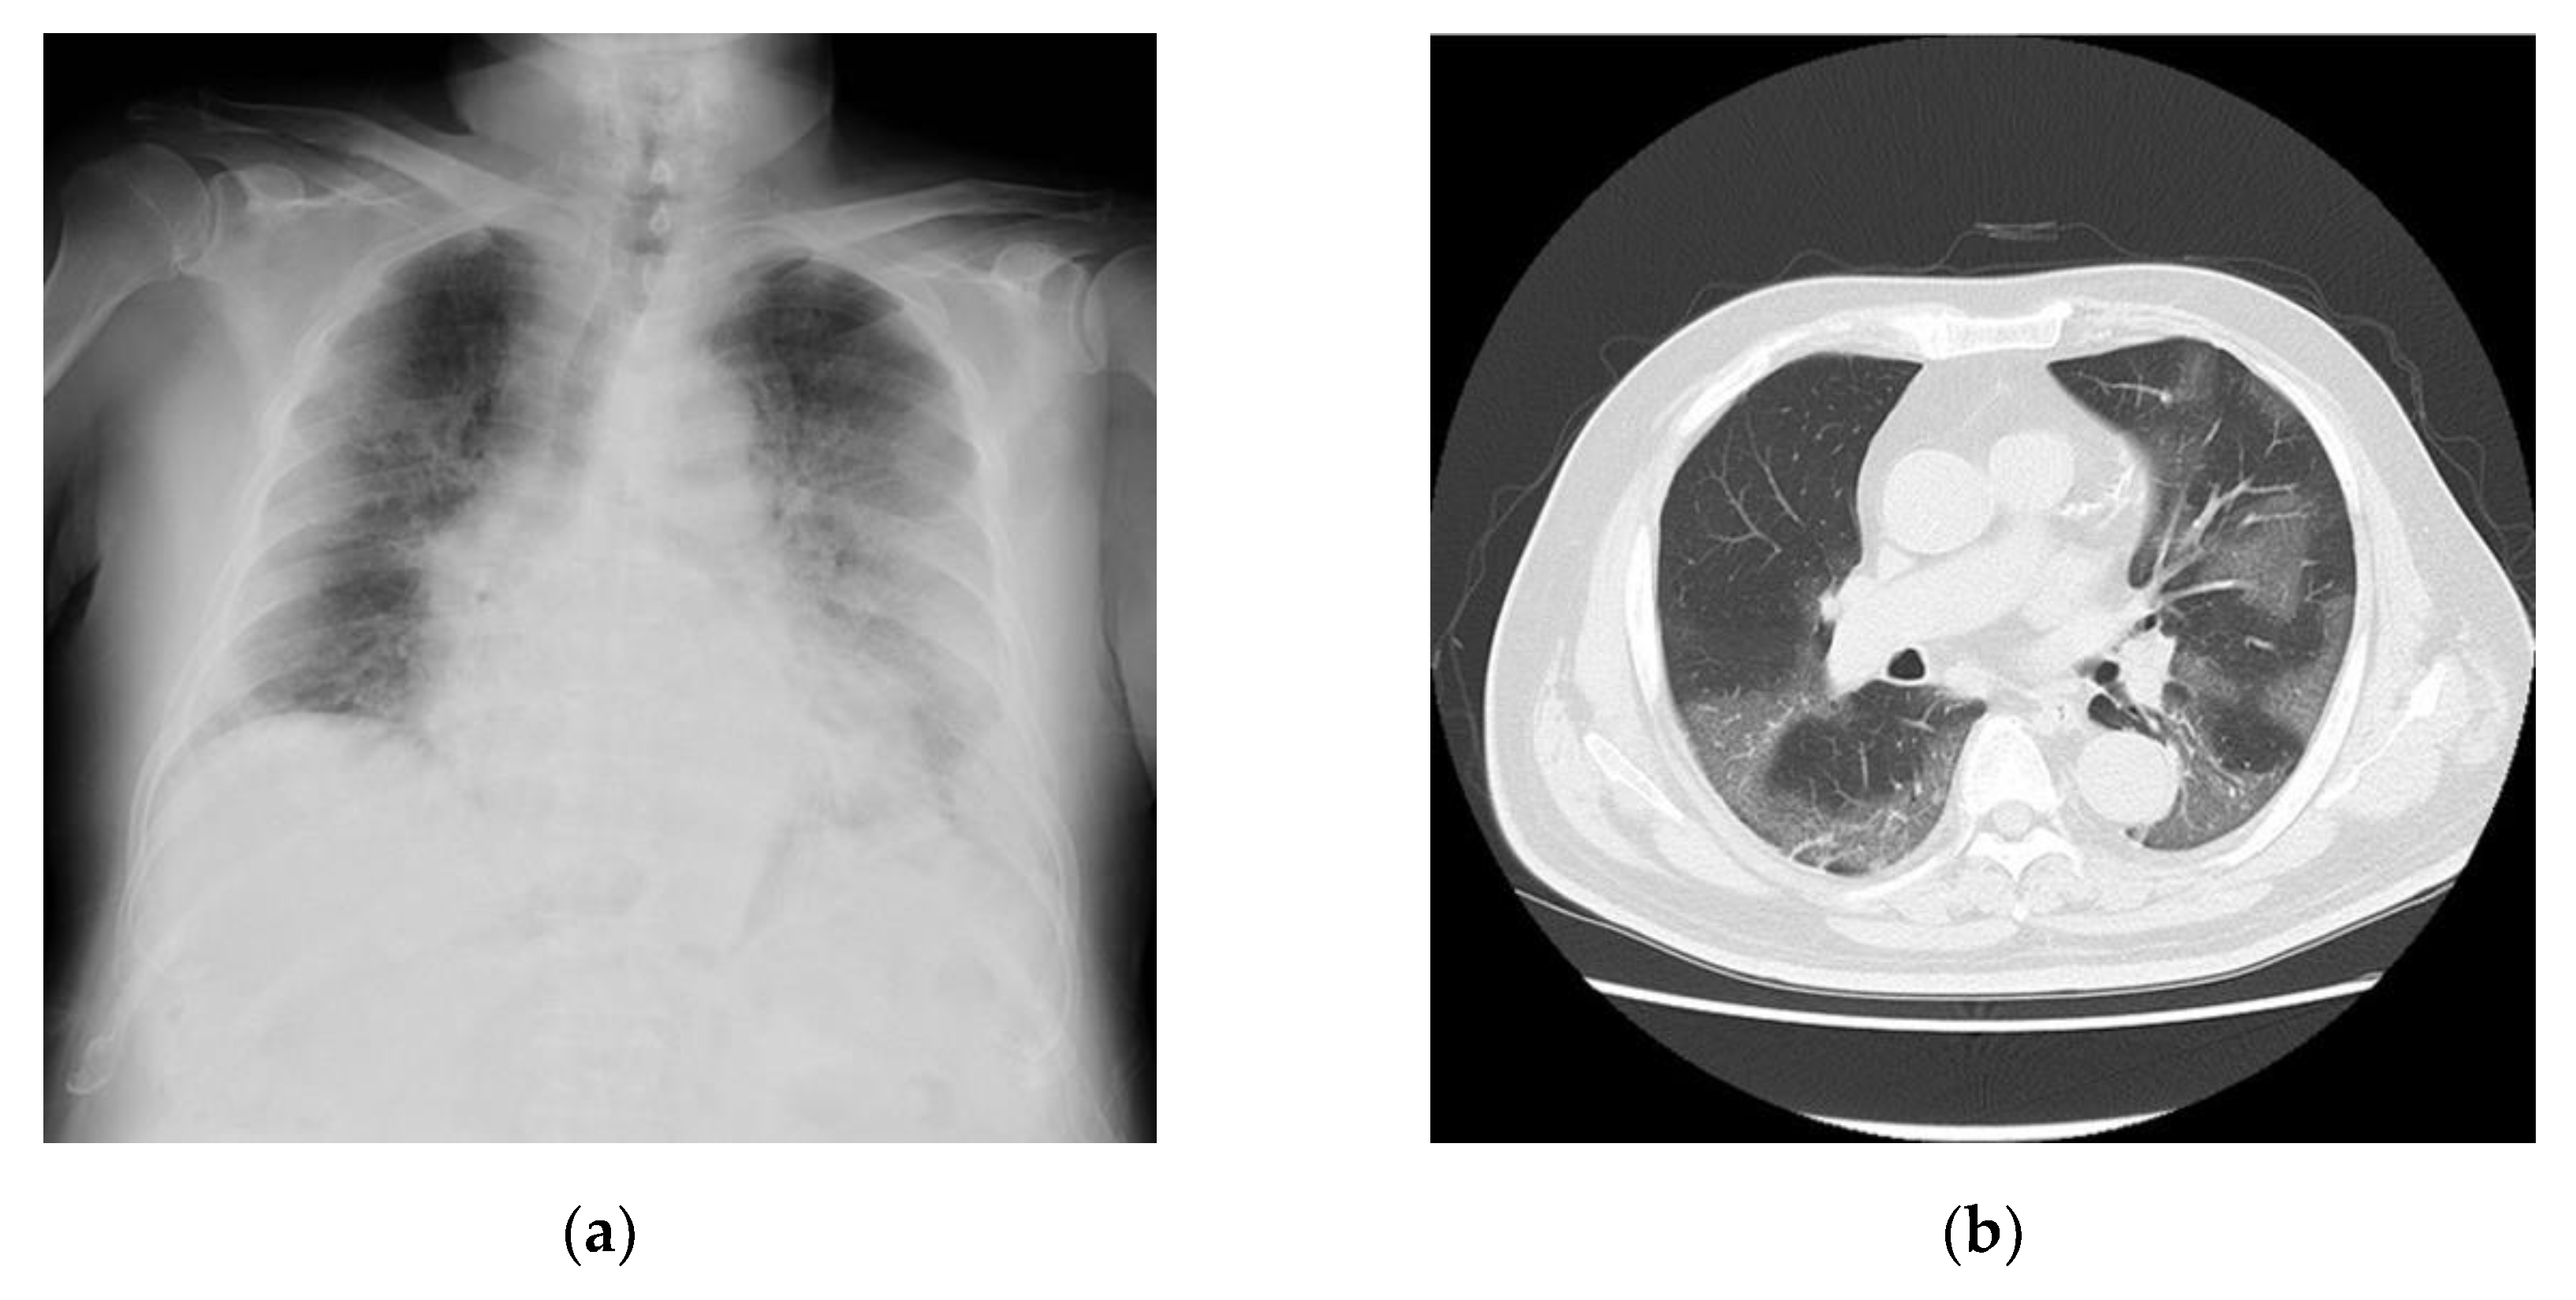

2.2. Case 2